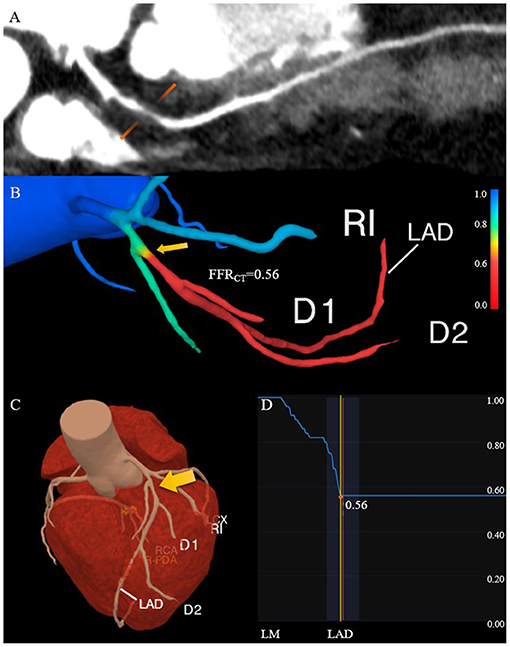

Fractional flow reserve (FFR) is the ratio of the pressure at the distal end of the stenosis to the pressure at the proximal end of the normal vessel in a state of maximum hyperemic condition. In recent years, FFR derived from CCTA (FFRCT) has used advanced fluid dynamics analysis method which combines the advantages of CCTA and traditional FFR (Figure 3). It is an image post-processing technology that applies hemodynamics to CCTA examination, which uses conventional standardized CCTA image data to evaluate the hemodynamic differences of coronary artery stenosis (66). Assuming that blood is an incompressible Newtonian fluid with constant density and viscosity, the flow and pressure in the coronary model volume can be calculated by the Navier-Stokes equations (12, 58). Three prospective clinical trials (67–69) all have verified that FFRCT can evaluate coronary artery stenosis from both anatomy and function. In addition, it has avoided the invasive operations of traditional FFR and the complications such as coronary artery tearing, bleeding, arrhythmia, myocardial infarction, and so on (70). This “one-stop” technology can fundamentally avoid unnecessary coronary angiography and revascularization. Moreover, it can provide more information for clinical practice and has the potential to replace other traditional methods recommended in clinical guidelines. As a long-term gatekeeper to guide revascularization, FFRCT is a new hot spot in clinical research (69, 71, 72).

Figure 3. Comprehensive assessment of the characteristics of high-risk plaque with CCTA. (A) The lesion in the proximal of the left anterior descending coronary artery has positive remodeling and low attenuation. (B) The FFRCT map derived from computational fluid dynamics shows a value of 0.56 distal to the stenosis, which indicates lesion ischemia. The transition from blue to red along the left anterior descending coronary artery indicates the decreasing trend of the FFRCT. (C) The 3D model diagram of the coronary artery, and the yellow arrow indicates the location of the high-risk plaque. (D) The curve of the FFRCT value from the proximal to distal of the left anterior descending branch. CCTA, coronary computed tomography angiography; FFRCT, fractional flow reserve derived from CCTA.

FFRCT, change in FFRCT across the lesion (ΔFFRCT), wall shear stress (WSS) and axial plaque stress are important hemodynamic parameters, which has been reported to be associated with the occurrence of adverse clinical events (13, 65, 66, 73–75). Lee et al. had demonstrated the role of these non-invasive hemodynamic parameters in identifying high-risk plaques leading to ACS by comparing adverse plaque characteristics and non-invasive hemodynamics parameters between culprit and non-culprit lesions (76). The adverse hemodynamics were defined as FFRCT ≤ 0.80, ΔFFRCT ≥ 0.06, WSS ≥ 154.7 dyn/cm2 or axial play stress ≥ 1606.6 dyn/cm2. The results showed that the FFRCT of culprit lesions was lower compared with non-culprit lesions, which was consistent with the findings of Ferencik et al. (77). While ΔFFRCT, WSS, and axial plaque stress are higher in culprit lesions, and ΔFFRCT has the highest incremental value. Moreover, Park et al. proved that ΔFFRCT has a powerful value in ACS risk prediction (78), indicating that lesion-specific hemodynamic parameters have greater influence on the occurrence of plaque rupture and ACS than that in vascular level. The value of WSS in identifying high-risk plaques has also been confirmed (79–81).